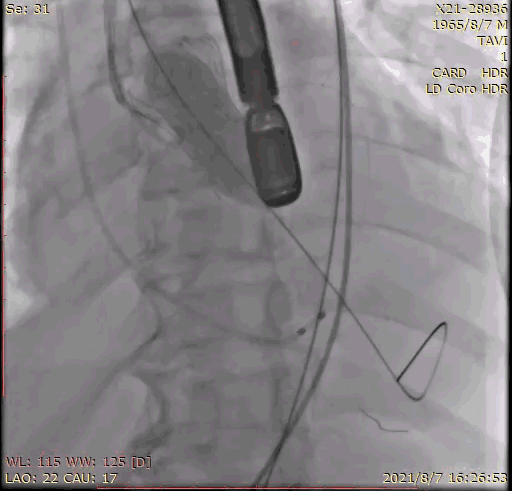

2.术前冠脉造影,提示左冠中段存在狭窄,TEE 见大量反流影;

6.经右桡动脉血管鞘送入6F JL4.0指引导管,送 Runthrough至前降支远端,后在GuidezillaII 支撑保护下送 4.0×18mm 支架至 LAD 近段;

7.根据术前评估及球囊预扩情况,选择 26mm 沛嘉 TaurusElite 瓣膜进行植入,第一次展开瓣膜位置偏下,全回收一次再次展开瓣膜,在 130 次/分快速起搏下释放瓣膜,同时将冠脉支架拉至左冠开口外约 9mm 处释放;